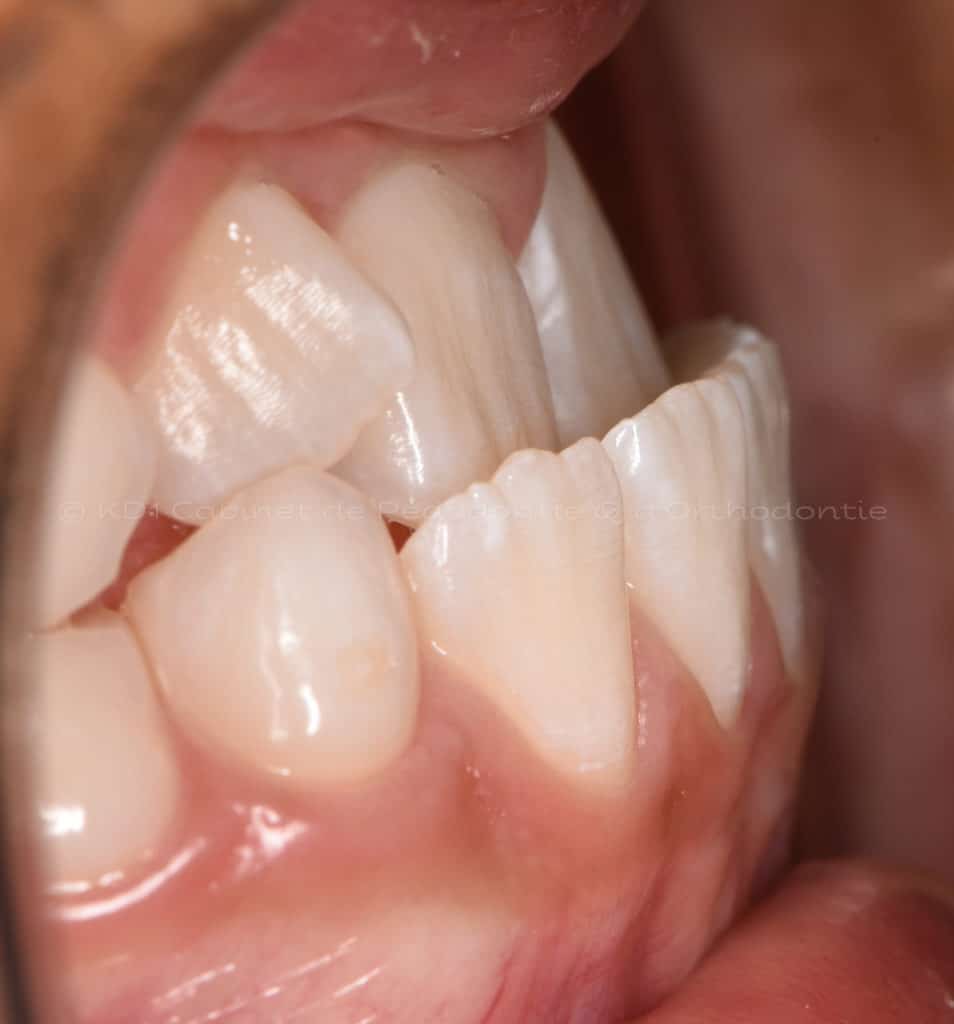

Correction des problèmes d’occlusion en dentition mixte, c.-à-d. à l’âge où l’enfant a des dents de lait et adulte, souvent entre l’âge de 7 ans et 9.5 ans. Le but de ces interventions n’est pas d’aligner les dents, car la dentition est en train de changer.

Cas #3 – Traitement avec un casque de traction maxillaire en dentition mixte (âge 9.5). Le but est de redresser les dents de devant (très penchées en avant) afin d’éviter les cassures de ces dents. Le recul de la dentition supérieure est possible avec ce dispositif extraoral. Un effet favorable indirect sur la mâchoire inférieure est à visible.